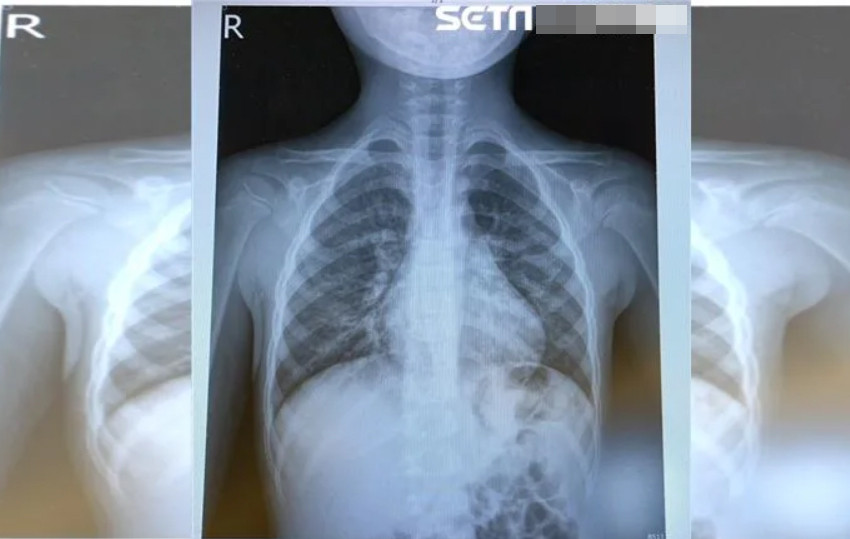

Số người nhiễm virus HMPV ảnh hưởng đến phổi tăng lên trong mùa đông năm nay của Trung Quốc. Ảnh: BSCC